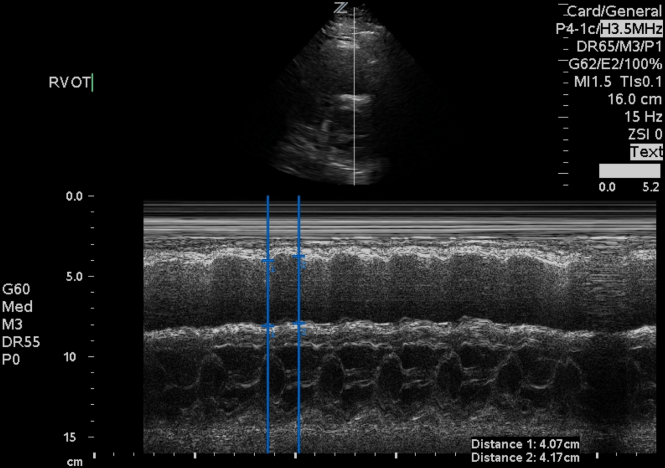

Well, don’t give up hope – introducing RVOT systolic excursion! This measurement is obtained using the parasternal short axis view at the level of the aortic valve.

It appears that measuring RVOT systolic excursion (as a percentage of end-diastolic RVOT diameter minus end-systolic RVOT diameter divided by end-diastolic RVOT diameter) is both specific and highly sensitive for acute PE. Analysis of right ventricular outflow tract systolic excursion showed that a value <24.3% can be found in acute pulmonary embolism patients with 100% sensitivity and 95.56% specificity (AUC = 0.987, P < 0.0001).